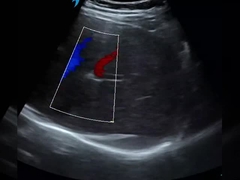

qualité Scanner tenu dans la main d'ultrason, Sonde sans fil d'ultrason fabricant de Chine

fournisseur de qualité Produits principaux